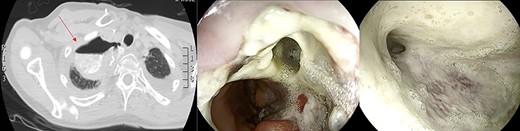

Anastomotic dehiscence was conservatively treated by EVAC therapy, placing the Esosponge in pleural space via an overtube (Fig. 2).

EVAC uses the main principle of negative pressure wound therapy by decreasing bacterial contamination and local edema while promoting perfusion and granulation tissue formation. The sponge can be placed in either an intraluminal or an intracavitary position across an internal fistula opening, using the overtube with a designated pusher. In our case, the sponge was always set inside the cavity because of the large size of the collection.